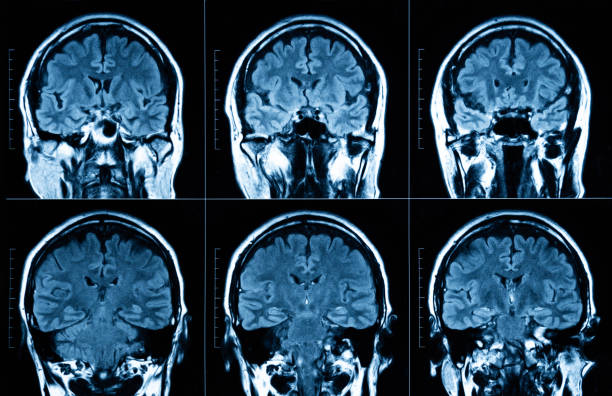

MRI scan human head Tomography

An analysis of cortical organization is forcing neuroscientists to rethink how we map the brain.